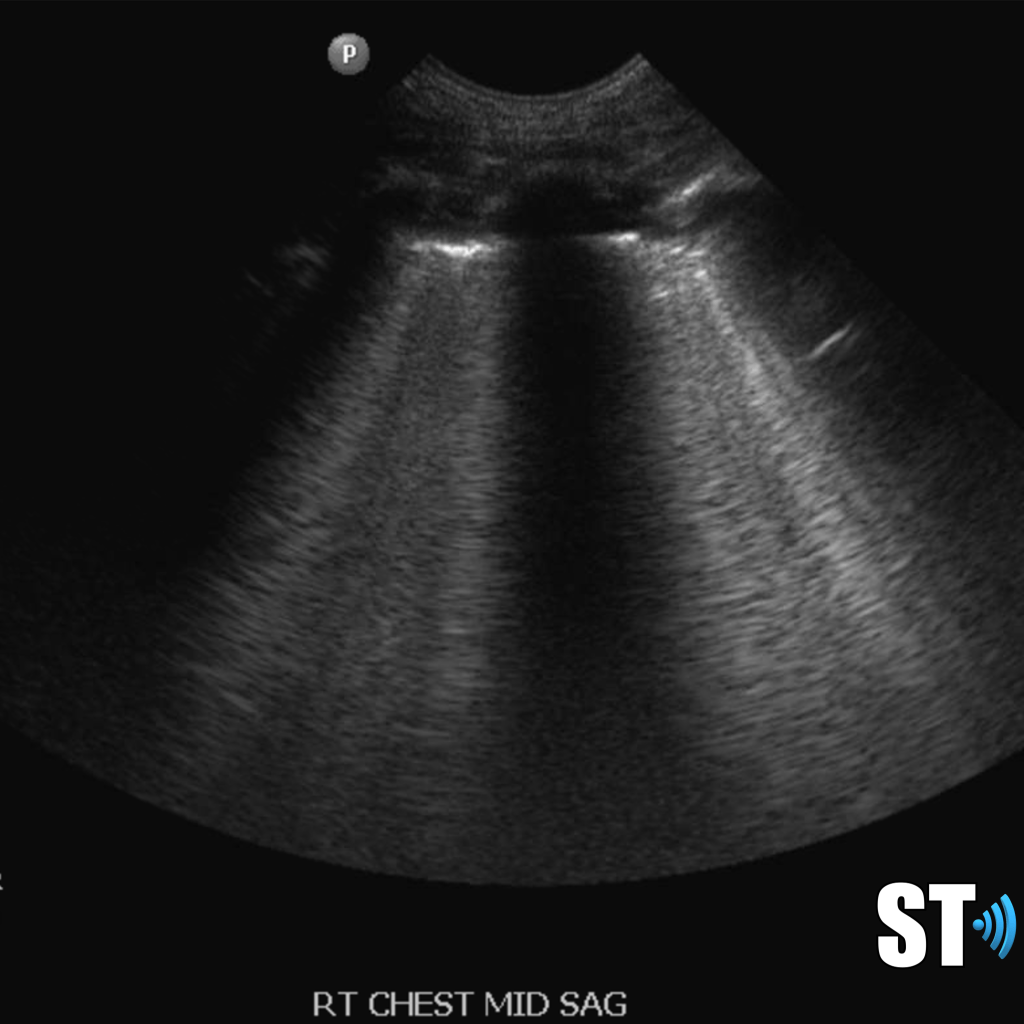

Moderate to large pleural effusion and pleural fluid anterior to lung

Large volume pleural effusion